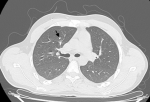

Diagnostic assessment: magnetic resonance imaging of the brain demonstrated an infiltrative thalamo-peduncular lesion with hyperintensity on T2/FLAIR sequences and faint enhancement on post-contrast T1, raising concern for an infiltrative high-grade glioma and creating diagnostic uncertainty (Figure 1, Figure 2). A stereotactic biopsy was subsequently performed. Initial histological evaluation suggested a high-grade glioma; however, immunohistochemical staining revealed strong positivity for CD117, PLAP, and OCT4, findings consistent with a pure germinoma (Figure 3, Figure 4). Staging with thoraco-abdominopelvic CT identified nonspecific pulmonary micronodules (Figure 5), while serum tumor markers remained within normal limits (Table 1). As shown above, the patient's LDH level is elevated compared to the reference range, while both β-HCG and α-FP are within normal limits. These values are important for the diagnostic evaluation and ongoing management of intracranial germ cell tumors.

Figure 5: chest computed tomography image showing a non-specific pulmonary micronodule: parenchymal window chest computed tomography image demonstrating a small non-specific pulmonary micronodule (arrow) without associated consolidation or mass effect